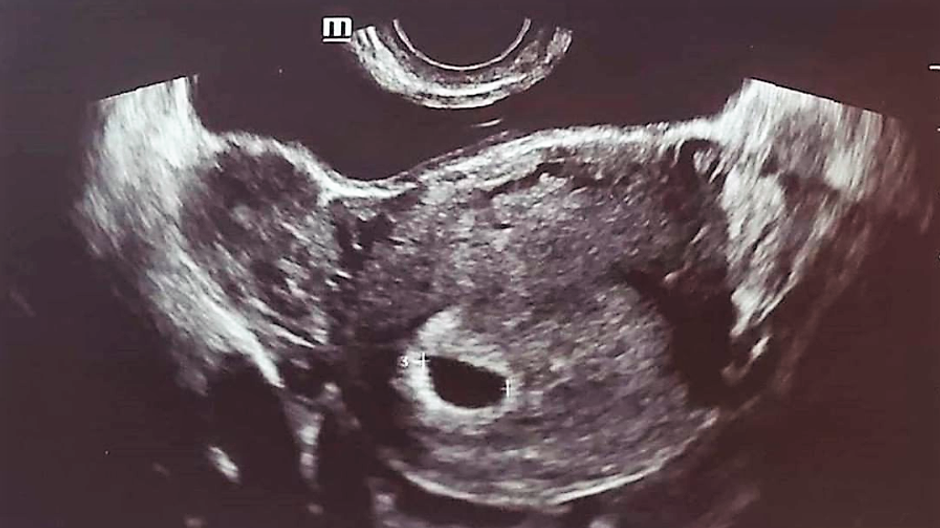

tehotenstvo ultrazvuk Amanda Bynes

Zdroj: Instagram/AB

Po správe o mega rýchlom zasnúbení 33-ročnej Amandy Bynes s  Paulom Michaelom, ktorého stretla na protialkoholickom liečení, herečka teraz šokuje ultrazvukovou snímkou na jej sociálnej sieti.

Fotka ultrazvuku zo sociálnej siete za okamih zmizla:

​Správy o rozchode vystriedala úplne iná fotka s komentárom: „Bábätko vo výrobe“. Obrázky boli za krátku chvíľu vymazané z oboch profilov a fanúšikov by iste neprekvapilo, keby išlo o ďalší z jej spôsobov ako získať pozornosť. No tentokrát očitý svedok potvrdil, že Amanda navštívila ambulanciu v Los Angeles a bola celkom rozrušená. Navyše, na obrázku z ultrazvukového vyšetrenia naozaj svietilo herečkino meno.